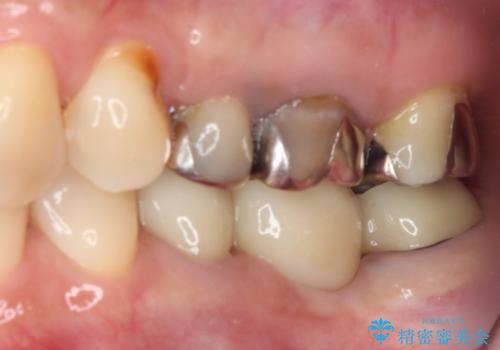

- 近医にて奥歯の抜歯が必要と言われたとのことで来院された患者様です。

診断の結果、奥歯は歯根が破折しており、抜歯が必要な状況でした。

インプラントあるいはブリッジによる補綴治療が考えられましたが、前後の歯が大きな銀歯であったため、オールセラミックブリッジにより3本の歯を審美的に仕上げることとしました。